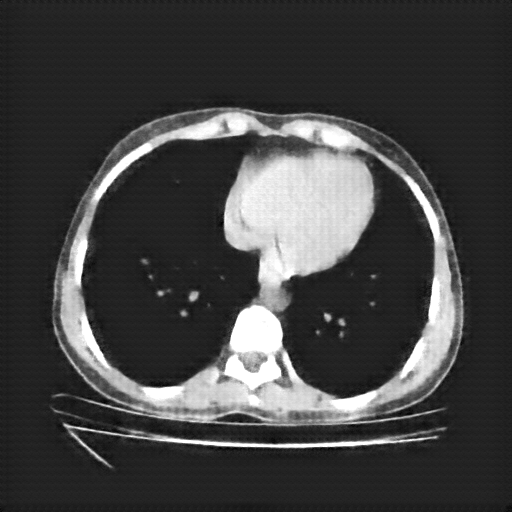

Original NATIVE CT scan (input)

Full window (WL 1023.5, WW 4095 β†’ Low βˆ’1024, High +3071)

Actual HU range: [-160.0, 240.0]